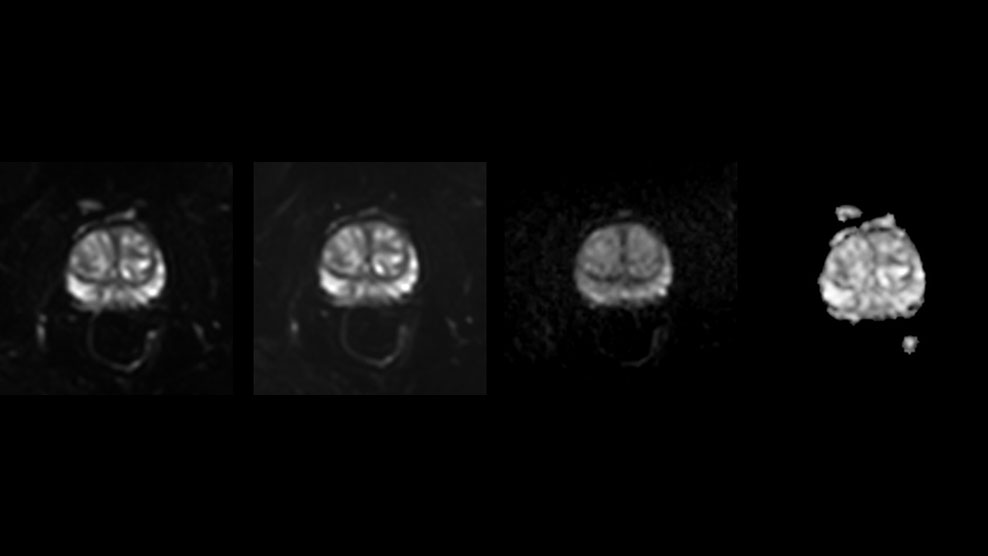

DMG recognizes MultiVane XD motion compensation is another Philips technique that contributes to image quality and scan efficiency. “We run MultiVane XD for motion-free imaging on almost all our T2-weighted brain scans, just to reduce any repeats we might get. We know our non-contrast brain scans are going to take 20 minutes almost every time,” Mr. Duffy says.

“Using MultiVane XD still allows us to turn on dS SENSE, which significantly cuts scan time compared to what we were doing before,” he adds. “We went from a 2.5 or 3-minute scan to a 1.5-minute scan with no loss in image quality. So, it not only reduces the motion, but also reduces scan time. That gives us a little bit of extra time to speak to our patients and explain the exam a little more.”